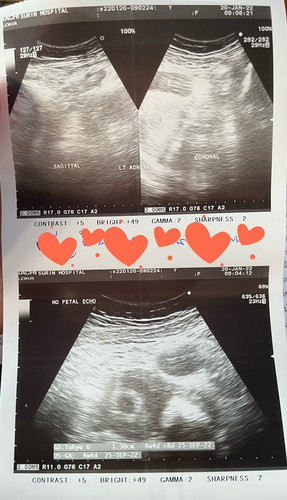

🤰🏻 4 weeks and 4 days. 🤰🏻

ซาวด์รอบแรก 06/01/65 ไม่เจอ ซาวด์รอบสอง 20/01/65 เจอถุงตั้งครรภ์ในมดลูก ดีใจและลุ้นมากๆ ขอให้แข็งแรงและมีพัฒนาการตามลำดับนะลูก ❤️❤️